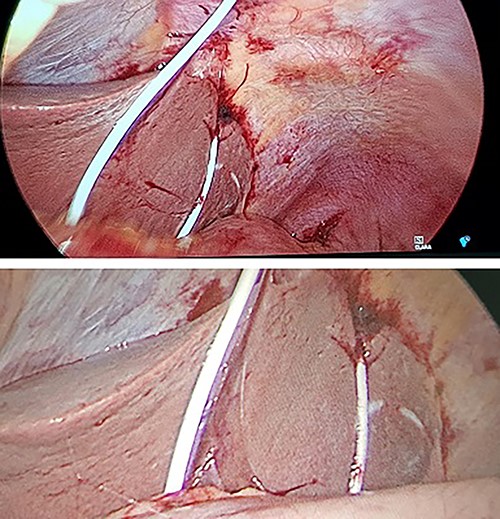

(A) Axial CT-angiogram: side drainage holes are apparent in the pericardium and the abdominal cavity; the drain courses anteriorly and abuts the medial aspect of the liver and stomach ~3 cm superiorly and medially to the course of the drain insertion forming a large loop; free gas is apparent at the right anterior liver; (B) sagittal CT-angiogram: subxiphoid approach with peritoneal entry; (C) coronal CT-angiogram: placement of catheter in pericardium; catheter traverses segment 2/3 liver.

The CT-angiogram showed no evidence of pericardial effusion, suggestive of successful treatment by drain placement (Fig. 1). It showed pneumo- and haemoperitoneum and that the drain appeared to course between the lesser curvature of the stomach and the liver with an intraperitoneal loop. There was no evidence of contrast leak to suggest active bleeding. A second CT of the abdomen with oral contrast provided no evidence of extravasation to suggest gastric perforation.